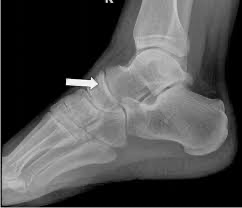

• An x-ray of a footDescription automatically generated